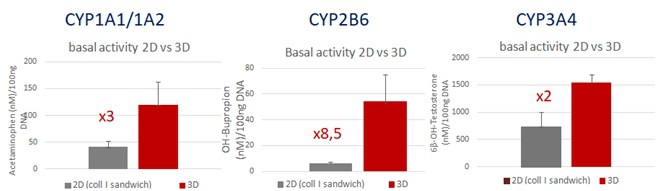

Maintains metabolic activities: Cryopreserved human hepatocytes

Basal CYP activity was analysed after 7 days of culture in 2D or in 3D.

Basal CYP activities are higher using BIOMIMESYS® Liver compared to 2D culture in sandwich.